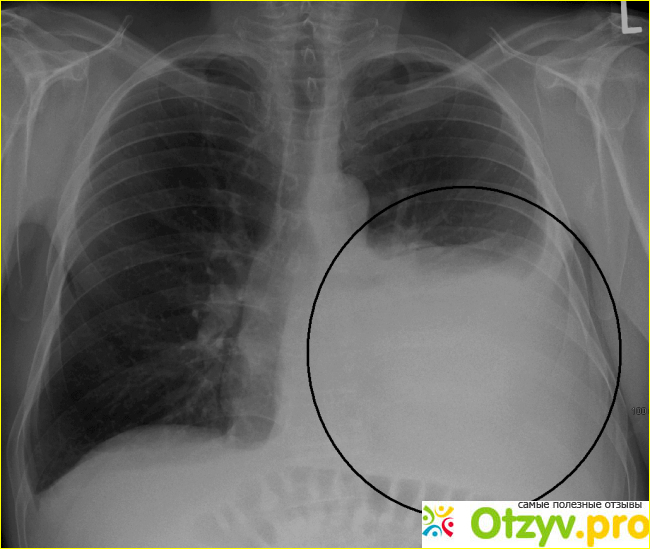

У человека с плевритом воспаление может вызвать то, что жидкость будет накапливаться меж мембранами. Это увеличение жидкости называется плевральным выпотом. Это может быть вызвано перепроизводством жидкости одной мембраной или сбоем другой мембраны для надлежащего слива жидкости. Плевральный выпот может облегчить симптомы плеврита, поскольку жидкость останавливает мембраны от решеток друг против друга. Однако накопление жидкости вокруг легких может вызвать сжатие легких и может привести к затрудненным дыханиям, таким как одышка или быстрое дыхание.

- рентген. Если врач хочет исключить другие проблемы, кроме плеврита, он может отправить вас на рентген, компьютерную томографию или даже ультразвук. Эти изображения могут показать, что это плеврит, который вызывает боль.